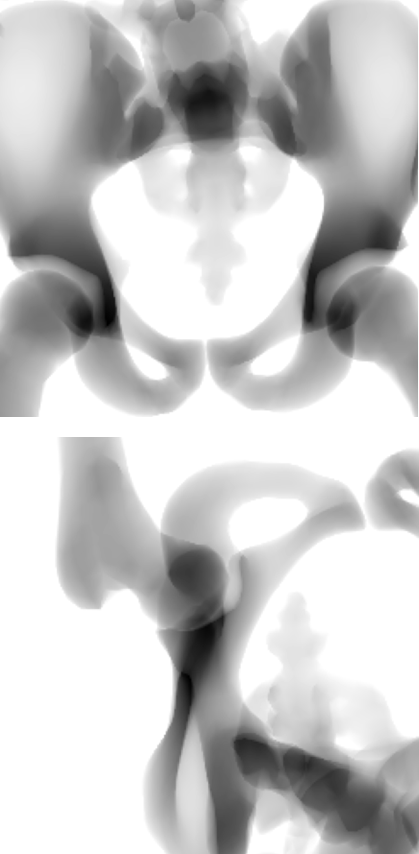

The SSM is registered to each patient from the dataset. This resulted in a base score with an average Hausdorff distance of 17.79\tsmm and a mean landmark error of 11.81\tsmm. The rotation and translation parameters obtained are assumed as the ground truth irrespective of the shape parameters. The 2D-3D reconstruction is tested by applying a random translation in the range of [-10,10]\tsmm and a rotation in the range of [-5,5] on all three axes for the SSM. The randomization is small due to the nature of the loss function being sensitive to changes only around a small region, such precision of initialization could be either provided manually or achieved with a network learning those initialization parameters. Fig. 3 shows sample outputs of our proposed method along with the quantitative results in Table 1. For evaluation, we consider only the images where the region of pelvis visible is greater than 50%percent5050\%.

Figure 3: Samples for 3D reconstruction from 2D projection images. (a) Target image, (b) Projection image with a random translation and rotation, (c) Projection image after registration, (d) Initial 3D overlay of template mesh, (e) 3D overlay of the meshes after registration, (f) NGC map after registration.